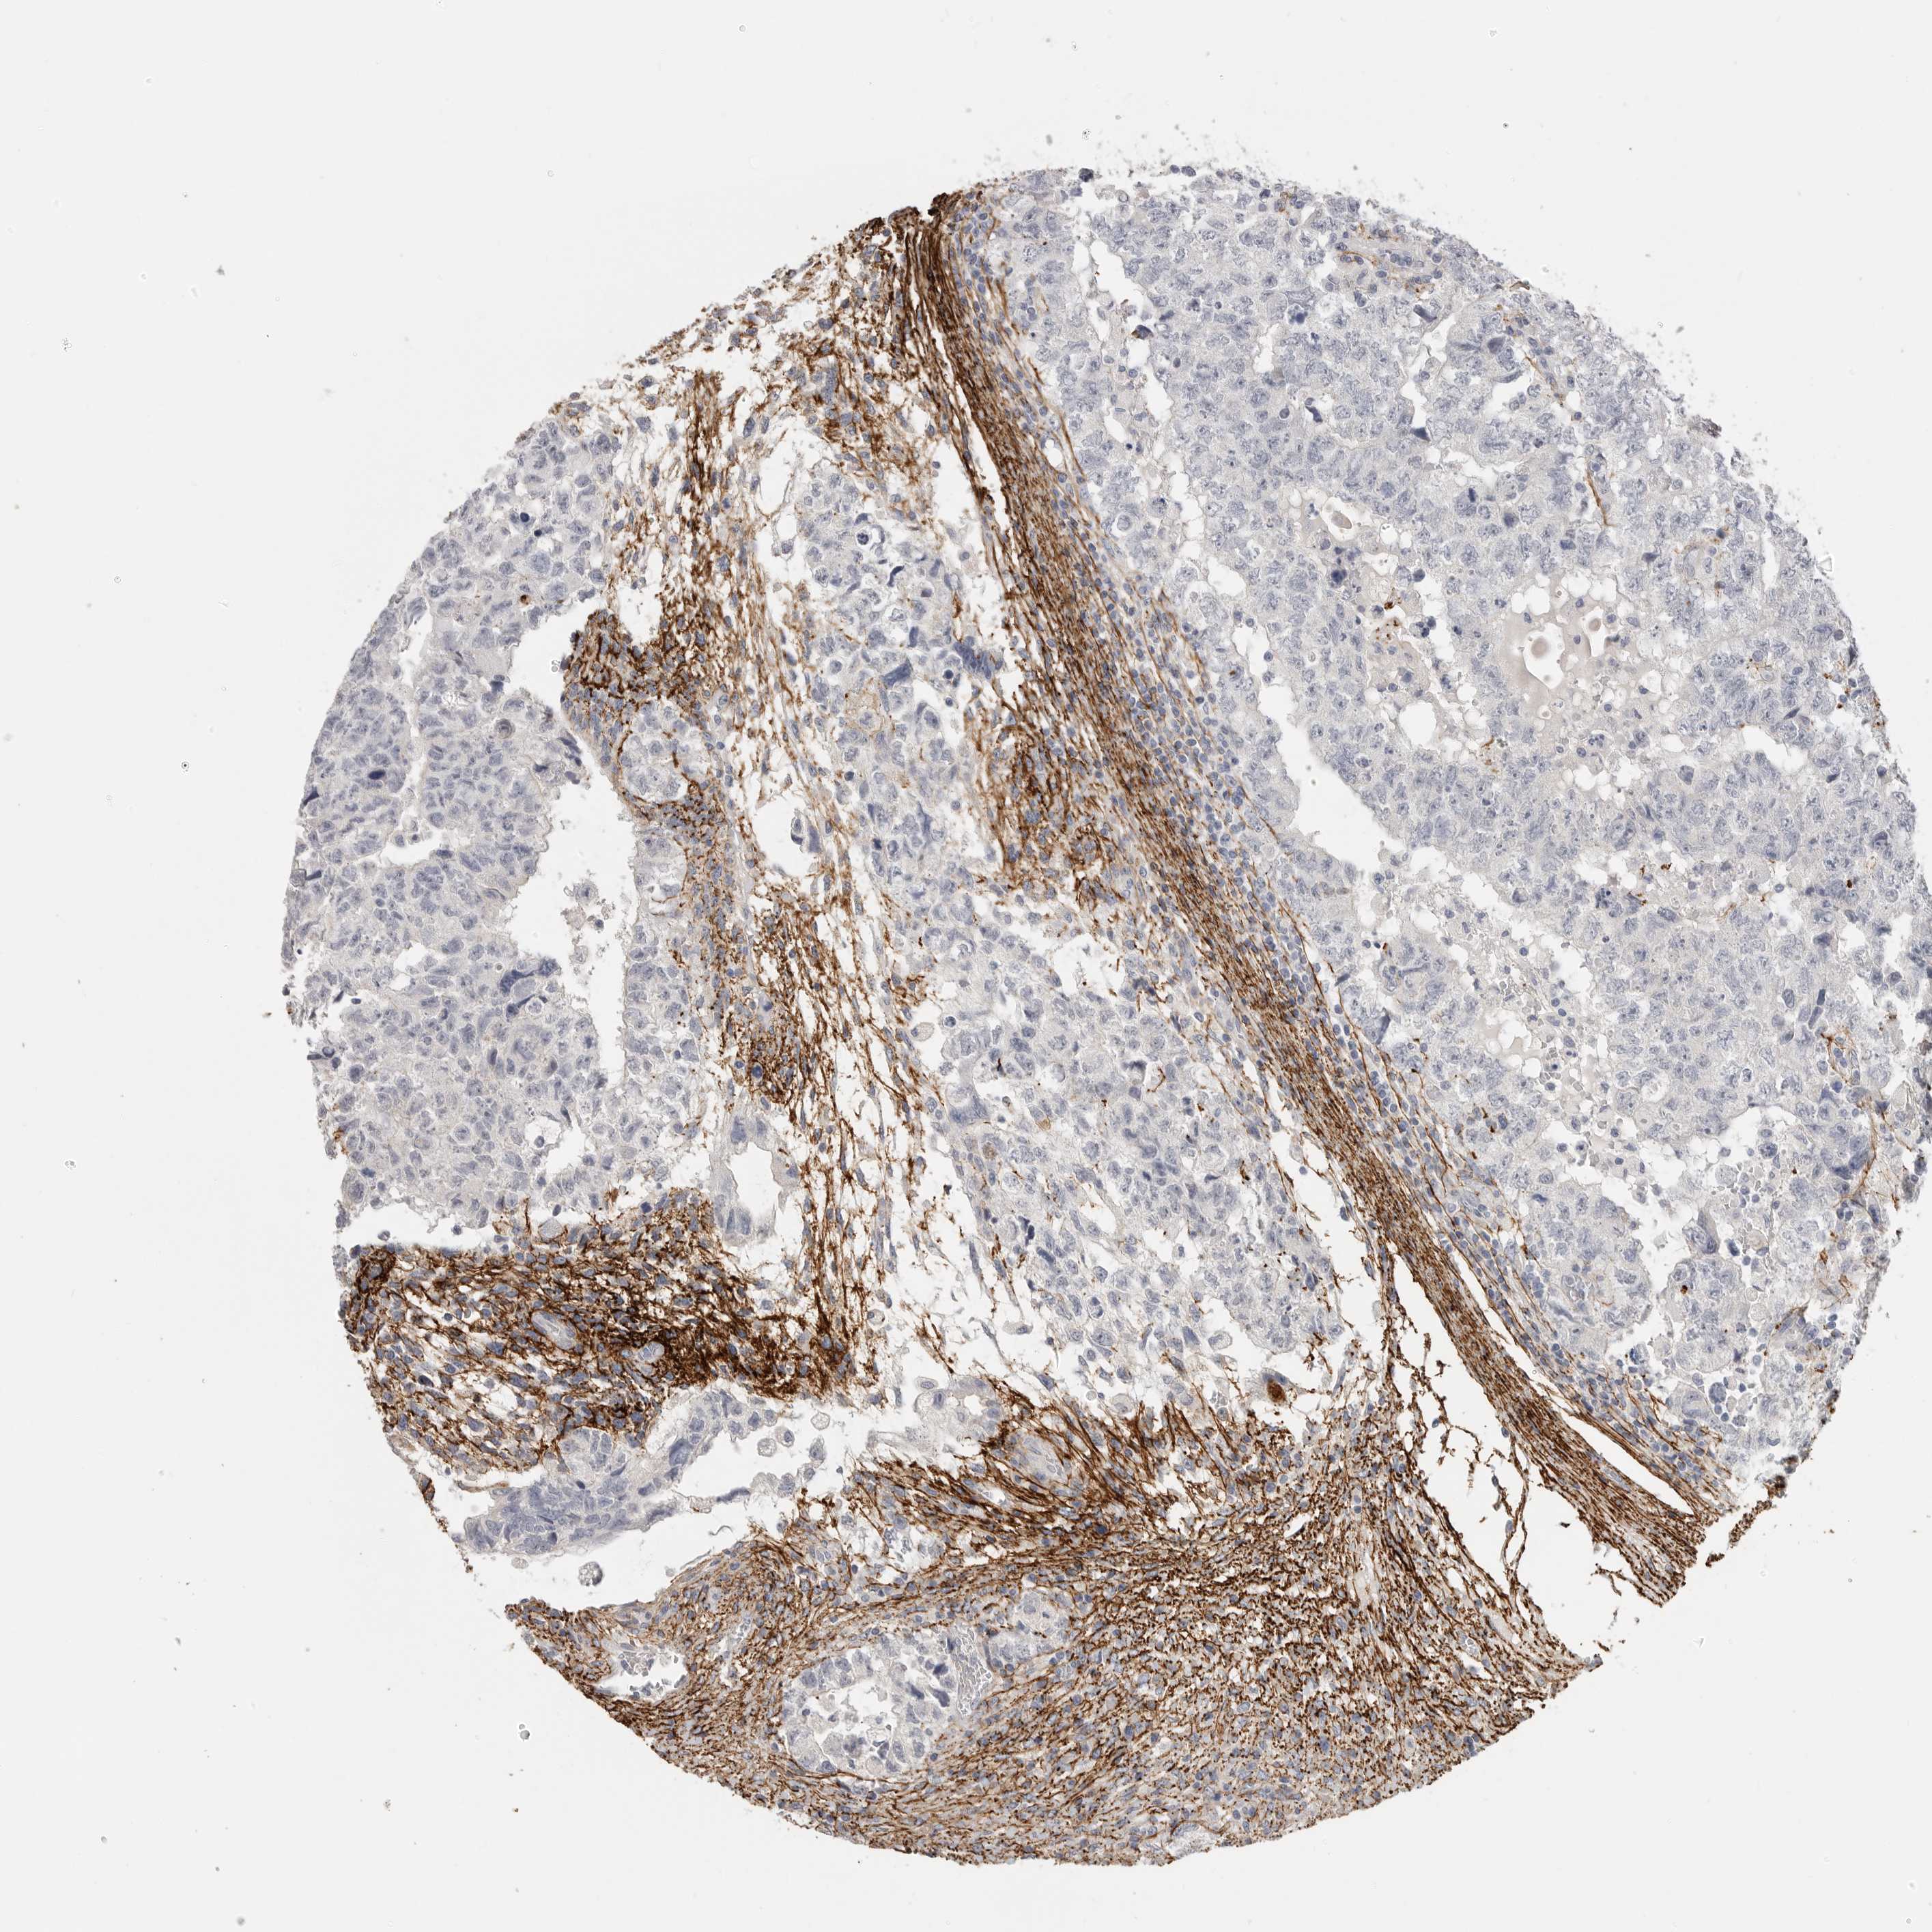

TESTIS CANCER - Protein expressioni

A mouse-over function shows sample information and annotation data. Click on an image to view it in a full screen mode. Samples can be filtered based on level of antibody staining by selecting one or several of the following categories: high, medium, low and not detected. The assay and annotation is described here.

Note that samples used for immunohistochemistry by the Human Protein Atlas do not correspond to samples in the TCGA dataset.

Antibody stainingi

Antibody staining in the annotated cell types in the current human tissue is reported as not detected, low, medium, or high, based on conventional immunohistochemistry profiling in selected tissues. This score is based on the combination of the staining intensity and fraction of stained cells.

Each image is clickable and will lead to virtual microscopy that enables deeper exploration of all samples and also displays staining intensity scores, fraction scores and subcellular localization as well as patient and tissue information for each sample.

Antibody HPA012853

Antibody CAB026401

Staining

High

Medium

Low

Not detected

Intensity

Strong

Moderate

Weak

Negative

Quantity

>75%

75%-25%

<25%

None

Location

Nuclear

Cytoplasmic/membranous

Cytoplasmic/membranous,nuclear

Carcinoma, Embryonal, NOS

Seminoma, NOS